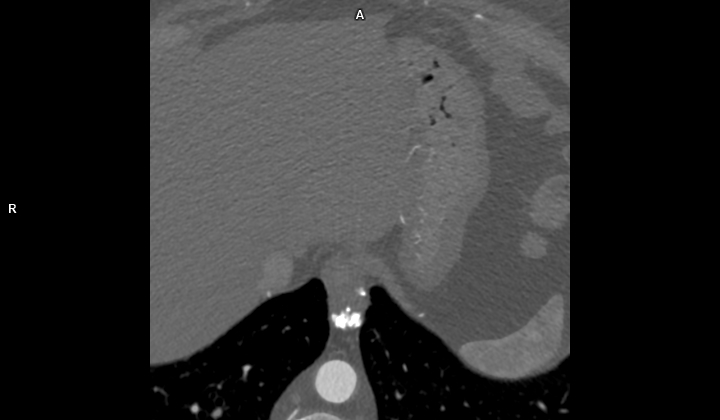

Figura 1: CT axial fără contrast